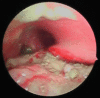

Case summary: A 6-year-old boy presented with ARDS from cement aspiration requiring high-pressure ventilation. He had further complications of tracheal injury with subsequent pneumomediastinum secondary to the alkali burn. He required ECMO to facilitate repeat bronchoscopy for cement particle washout and to enable recovery from ARDS and tracheal injury.

Conclusion: This case highlights the need to perform early bronchoscopy and gastrointestinal endoscopy for injury assessment and foreign body removal in alkali burns. It also emphasizes the value of ECMO support for respiratory failure and facilitating bronchoalveolar lavage when it is not otherwise tolerated.